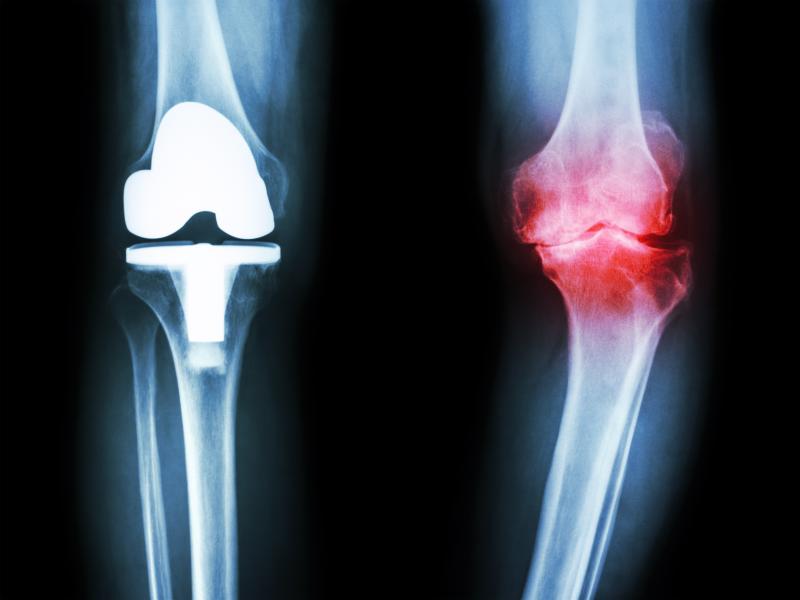

Treatment with tocilizumab leads to better suppression of joint erosion progression as compared to etanercept in patients with rheumatoid arthritis (RA), reports a recent study.

Researchers enrolled 187 patients, of whom 106 (mean age 62.8 years, 81 women) were treated with tocilizumab and 81 (mean age 51.3 years, 65 women) with etanercept. Joint destruction was measured using x-rays. Patients were also evaluated using the clinical disease activity index (CDAI) and modified health assessment questionnaire (mHAQ).